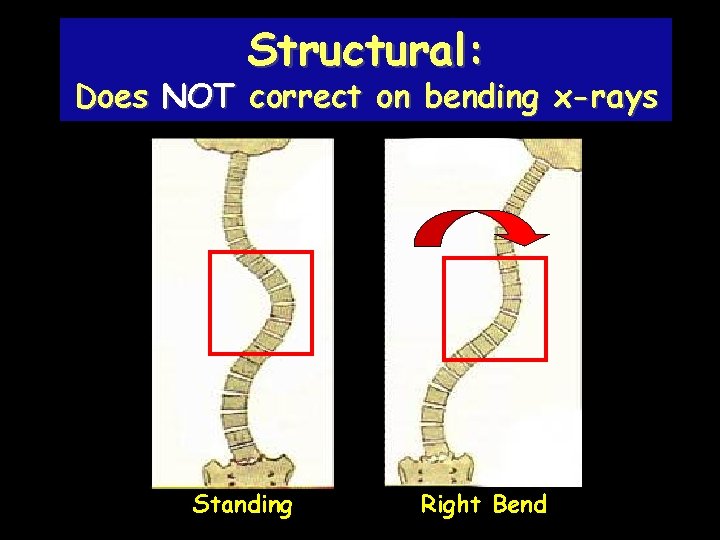

Structural: Does NOT correct on bending x-rays Standing Right Bend